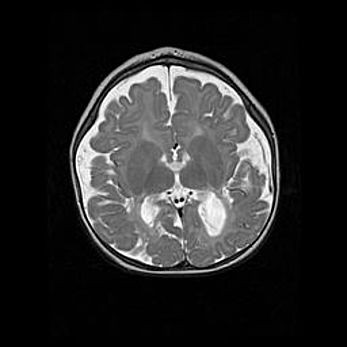

Множественные кисты обоих полушарий головного мозга, наибольшая из них в правой затылочной области. Ассиметричная атрофическая гидроцефалия.

Возраст: 7 месяцев

Вес: 5660 г

Пол: мужской

Окружность головы: 41,5 см

Срок гестации: 28-29 недель

Кисты головного мозга развиваются в результате многоочаговых некрозов вещества мозга и возникают вследствие перенесенной перинатальной инфекции, менингитов, энцефалитов, асфиксии, родовой травмы, расстройств мозгового кровообращения различного генеза. Образованию кист в веществе головного мозга плодов и новорожденных способствуют такие факторы, как высокое содержание в нем воды, недостаточная (или отсутствие) миелинизация и слабая астроглиальная реакция на повреждение.

Кисты могут сочетаться с гидроцефалией и другими поражениями головного мозга.